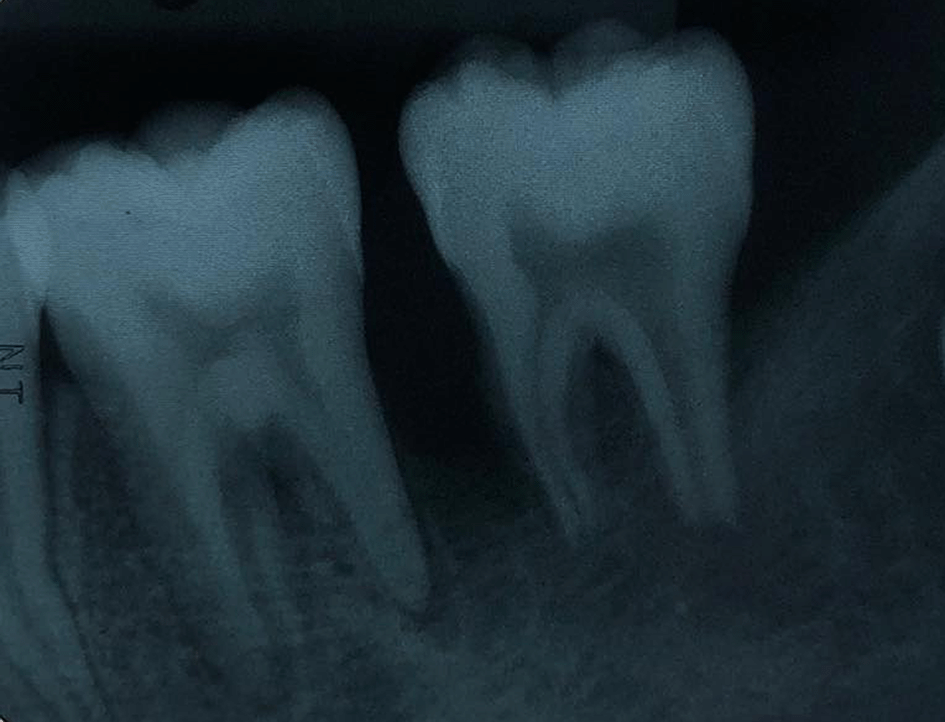

The periapical radiograph showed distinct periapical bone destruction of tooth no. 36 and tooth no. 37 (Figure 2).

The periapical radiograph demonstrating alveolar bone loss at tooth no. 36 and tooth no. 37.